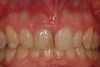

Fig 12. At 8 years post-treatment, the results of the minimally invasive approach remain an ideal esthetic implant placement, without visible damage or scar tissue from the flapless approach or connective tissue graft to thicken the biotype.

Figure 12